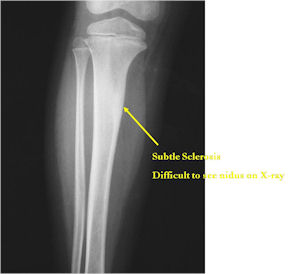

Plain X-Rays:

- Lucent nidus surrounded by a zone of marked sclerosis

- The nidus may demonstrate mineralization/ossification usually from the center outward that appears as a central zone of density within the nidus

- A nidus that is heavily ossified may blend in with the surrounding sclerosis and be difficult to detect on a plain x-ray.